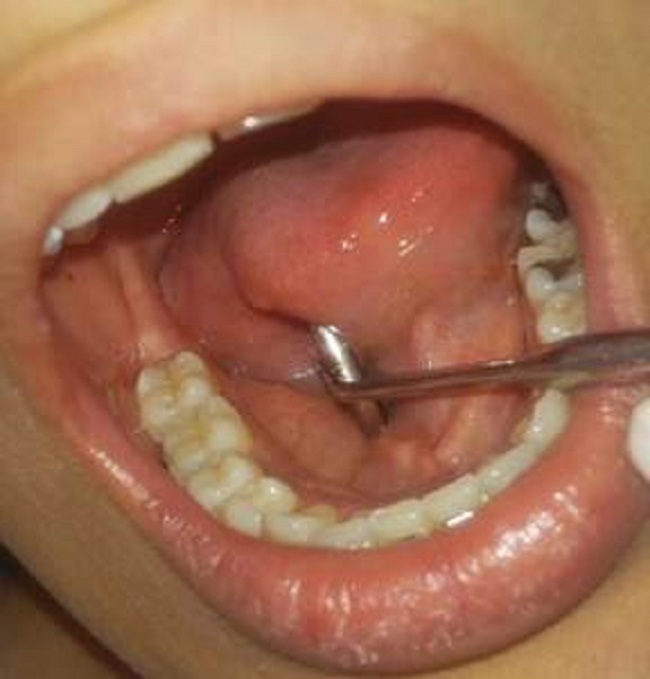

Al control posparto foto 4, no se observaron recidivas y hubo mejoría de la condición periodontal aun con el restablecimiento del tratamiento ortodóntico.

Aspecto gingival después del parto, reintegro de tratamiento ortodoncia

Foto 4

Fuente: propia de las y los autores.